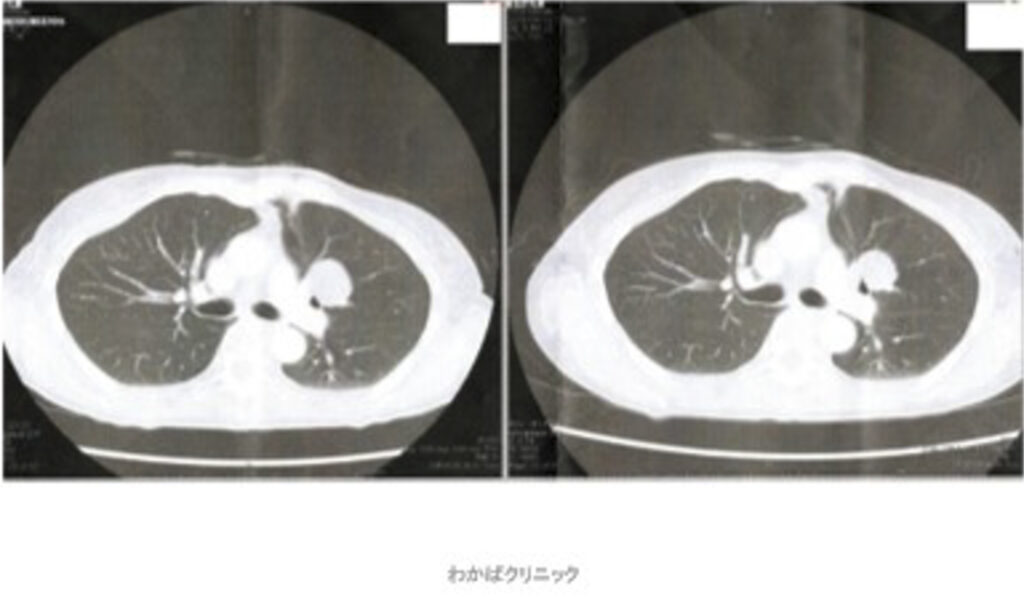

- 西洋医学的な効果判定(必ず必要です)

- CT・MRI・超音波検査 他